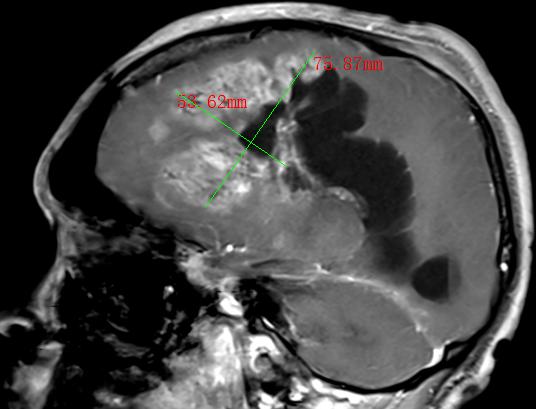

大脑是人体的“司令部”。在肿瘤大家族中,脑肿瘤对人体健康的威胁较大,而且在很短的时间内就会出现“整个人都不好”的情况,如出现双目失明、失...